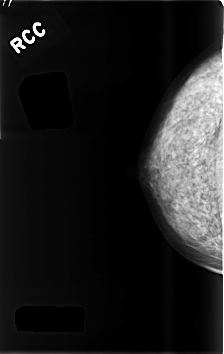

C_0480_1.RIGHT_CC

RIGHT_CC LINES 4592 PIXELS_PER_LINE 2904 BITS_PER_PIXEL 12 RESOLUTION 50 NON_OVERLAY